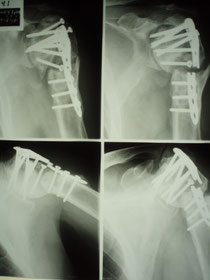

左のレントゲンは短縮転位 (受傷時) 右は整復操作をして骨片が重なり合っている状態

整復後包帯と装具で固定。当初は週に2、3回来院してもらいその都度固定は取り外し、体を洗いました。